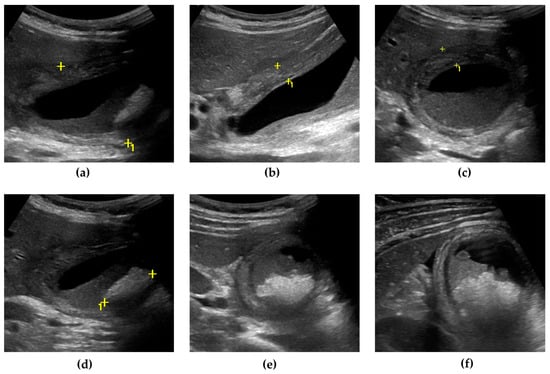

4.3. Imaging Findings

- Maddu, K.; Phadke, S.; Hoff, C. Complications of cholecystitis: A comprehensive contemporary imaging review. Emerg. Radiol. 2021, 28, 1011–1027. [Google Scholar] [CrossRef] [PubMed]

- Mencarini, L.; Vestito, A.; Zagari, R.M.; Montagnani, M. New Developments in the Ultrasonography Diagnosis of Gallbladder Diseases. Gastroenterol. Insights 2024, 15, 42–68. [Google Scholar] [CrossRef]